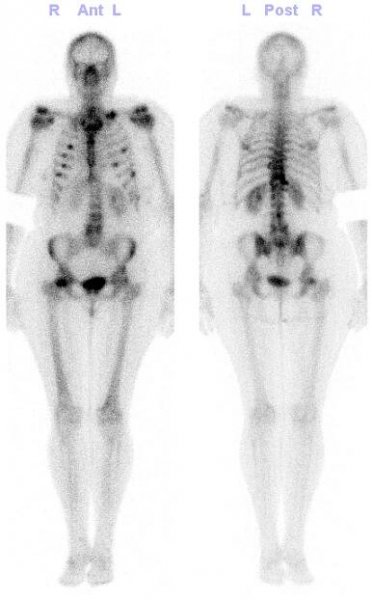

Obrázek č. 3: Celotělová scintigrafie skeletu

Obr. č. 2: Celotělová scintigrafie skeletu v kostní fázi vyšetření – mnohočetná ložiska zvýšené kostní přestavby ve výše uvedených lokalizacích.